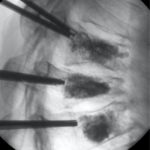

Our unique day case surgery allows our patients to be up and about within a few hours of their surgery and are able to go home the same day. View more Patient Stories.